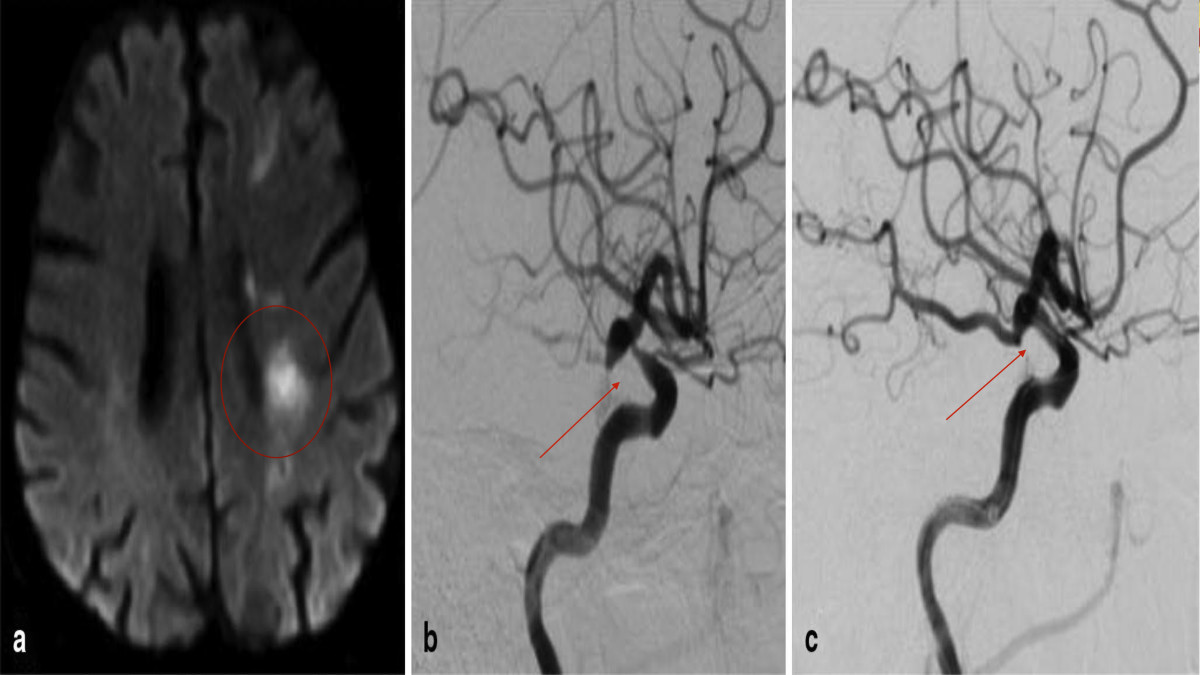

Στενώσεις ενδοκράνιων αγγείων – Ενδείξεις αντιμετώπισης

• Στενώσεις ενδοκράνιων αγγείων – Ενδείξεις αντιμετώπισης